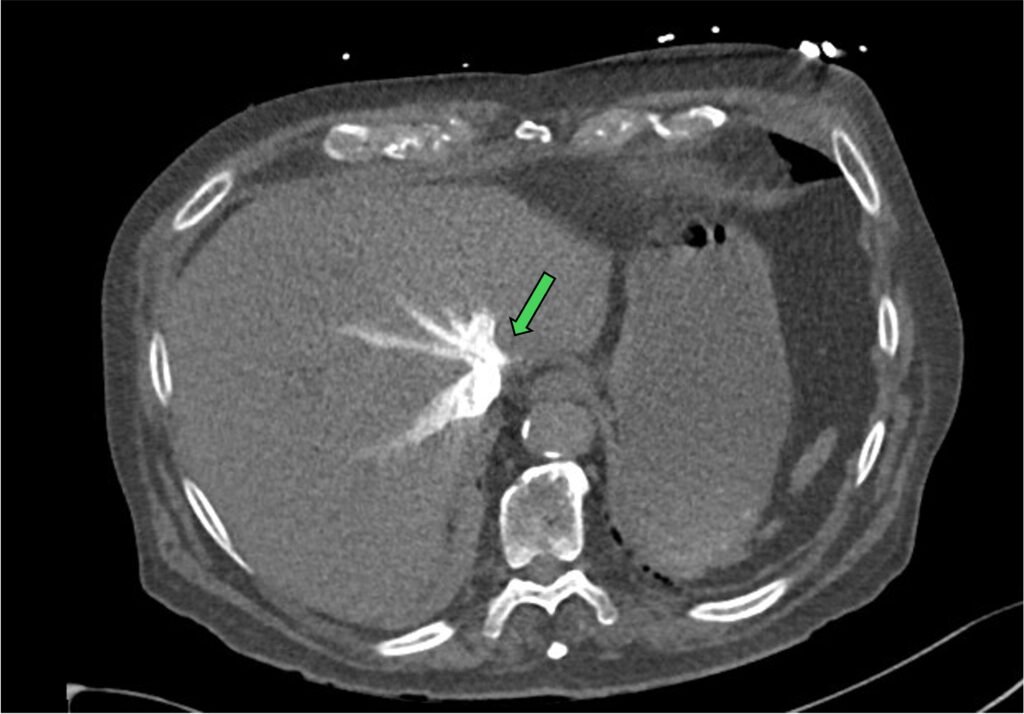

- contrast reflux to IVC and hepatic vein

Figure 11: contrast reflux in hepatic vein